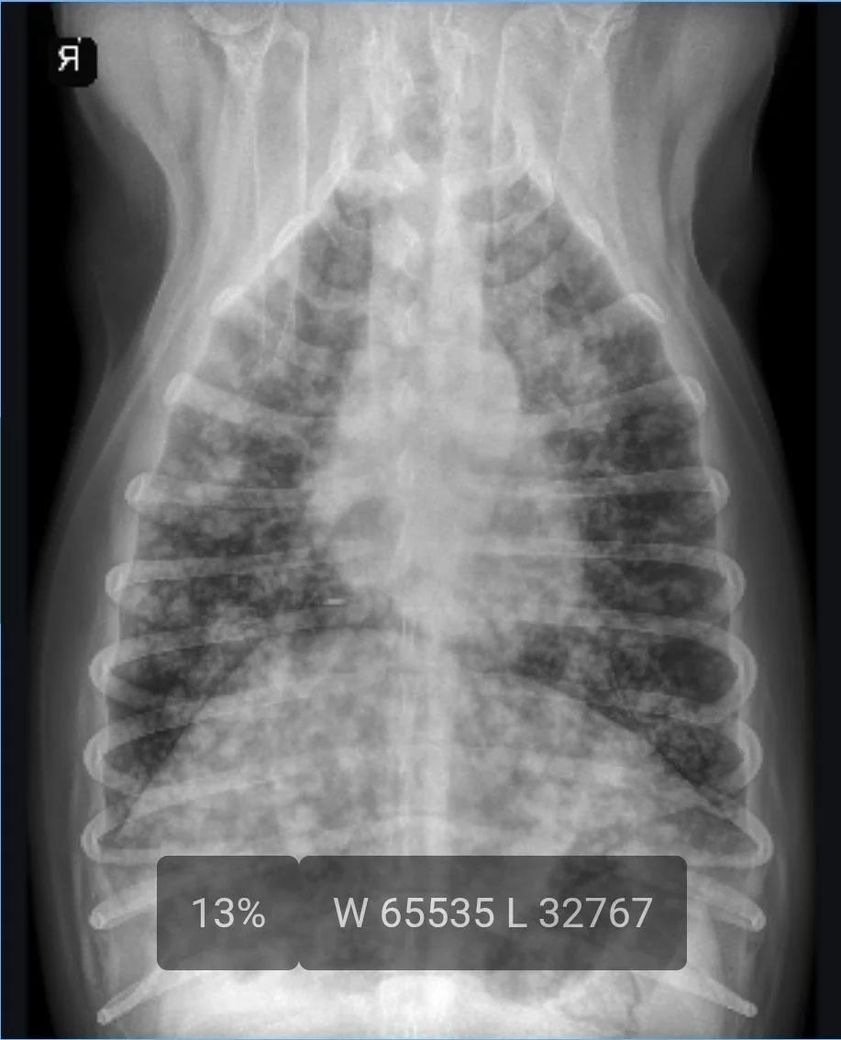

첨부한 사진은 제 강아지 사진은 아닙니다.

다만 제 강아지의 폐 흰색 영역이 저것보다 좀 더 많아 보였습니다.

부신 수질종양의 전이로 인한 폐 결절이 있던 강아지였습니다.